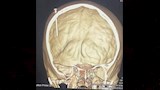

وأوضح أن الفحص الإكلينيكي وأشعة الـ CT أظهرا وجود مسمار معدني مغروز بزاوية رأسية في العظام الجدارية الأمامية للجمجمة، ممتدًا بعمق نحو القشرة الدماغية، مما يشكل خطورة بالغة على حياته.

وأضاف عرفة أنه بعد إجراء التحاليل والإشعاعات اللازمة، تم إدخال الطفل لغرفة العمليات. تم إجراء فتح جراحي دقيق حول الجسم المعدني، واستئصال جزء عظمي يحتوي على المسمار لتجنب أي إصابة إضافية للمخ أو الأوعية الدموية المجاورة، واستمرت العملية نحو 5 ساعات، وبعدها تم نقل الطفل إلى غرفة العناية المركزة.